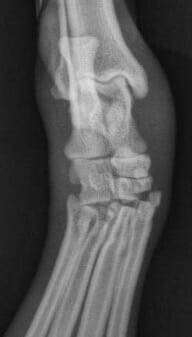

La radiographie simple peut être utile pour évaluer la présence d'une tuméfaction focale des tissus mous et la radiographie "sous contrainte" peut être utile pour documenter l'instabilité de l'articulation en cas de lésion ligamentaire importante ( Figure 2).

La tomodensitométrie (TDM) fournit beaucoup plus d'informations que les radiographies simples, en particulier dans les cas chroniques où des zones de minéralisation dystrophique peuvent s'être formées. La tomodensitométrie est inestimable dans les cas de traumatismes aigus qui peuvent avoir subi des lésions d'avulsion subtiles. L'échographie est devenue la modalité initiale de choix pour l'évaluation d'une variété de lésions musculo-tendineuses. En termes généraux, les régions hypoéchogènes représentent des lésions récentes et montrent des régions d'hémorragie et/ou de liquide, tandis que les régions hyperéchogènes représentent des régions de fibrose et de tissu cicatriciel plus typiques d'une lésion chronique Figure 3). L'échographie peut également fournir des informations supplémentaires en temps réel pendant que le tissu concerné est soumis à différentes amplitudes de mouvement.